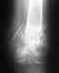

Моей маме 78 лет. Две недели назад случился перелом шейки бедра слева.

Изучив все материалы и рассмотрев все снимки в интернете я пришла к убеждению , что протез поставлен не корректнно ( мягко сказано)Всвязи с этим у меня назрели логические вопросы. Как обойтись без повторных вмешательств? с первых дней полная нагрузка. Домой забрала - вожу на коляске. Все свежее - не ровен час выскочит.

Это всего лишь снимок в боковой проекции. Никаких признаков неправильности установки протеза не содержит. Соответственно, ни о каких повторных вмешательствах речи нет. после заживления раны надо пациентку вернуть к ее обычному двигательному режиму. Ну и следовать рекомендациям лечащего врача.